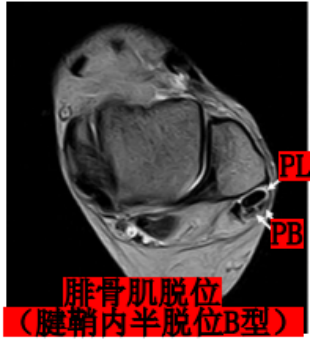

Raikin等学者提出将腓骨沟内腱鞘内半脱位不伴有腓骨上支持带损伤划为腓骨脱位的亚系。这些腱鞘内半脱位共有两型:

A型:腓骨肌腱无撕裂,肌腱暂时换位;

B型:腓骨短肌存在纵向撕裂,腓骨长肌腱自撕裂处半脱位。

MRI:能更清楚地显示软组织损伤情况,如支持带撕裂和腓骨肌腱半脱位。对于指导临床治疗及后期随访观察疗效具有重要参考价值。